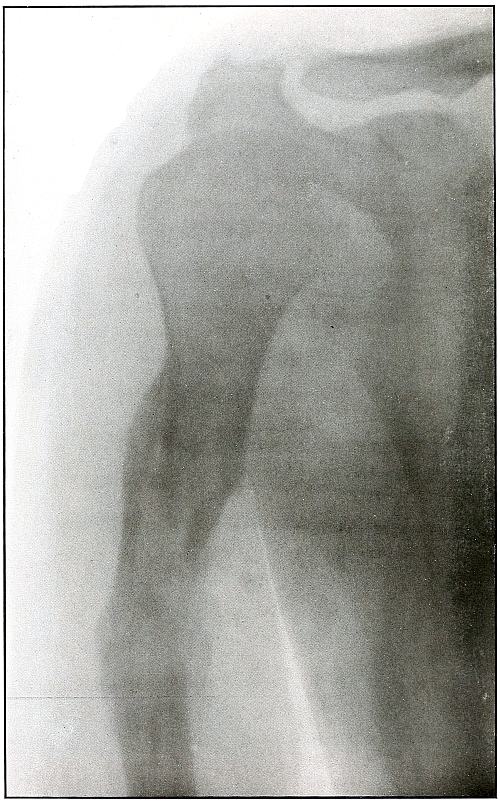

Plate 8.

[Pg 27]

Rifle—Plate 8.

UPPER EXTREMITY.

Compound Fracture of the Humerus

in Advanced State of Repair with Callus Formation.

Wound of entrance, just above middle of anterior aspect of arm.

Wound of exit, about the same height, posteriorly.

The course of the missile was anteroposterior, with high velocity of

short range through the bone with a splitting effect, leaving a few

fragments, large and small, which were not much displaced and caused

but little deformity.

Wound was not infected. The absorption of smaller and the overlapping

of larger fragments caused some shortening.

Treatment, expectant.

Results, favorable.